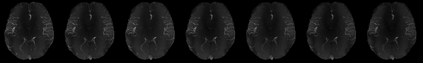

Magnetic Resonance Imaging (MRI) has excellent soft tissue contrast but is hindered by an inherently slow data acquisition process. Compressed sensing, which reconstructs sparse signals from incoherently sampled data, has been widely applied to accelerate MRI acquisitions. Compressed sensing MRI requires one or more model parameters to be tuned, which is usually done by hand, giving sub-optimal tuning in general. To address this issue, we build on previous work by the authors on the single-coil Variable Density Approximate Message Passing (VDAMP) algorithm, extending the framework to multiple receiver coils to propose the Parallel VDAMP (P-VDAMP) algorithm. For Bernoulli random variable density sampling, P-VDAMP obeys a "state evolution", where the intermediate per-iteration image estimate is distributed according to the ground truth corrupted by a zero-mean Gaussian vector with approximately known covariance. To our knowledge, P-VDAMP is the first algorithm for multi-coil MRI data that obeys a state evolution with accurately tracked parameters. We leverage state evolution to automatically tune sparse parameters on-the-fly with Stein's Unbiased Risk Estimate (SURE). P-VDAMP is evaluated on brain, knee and angiogram datasets and compared with four variants of the Fast Iterative Shrinkage-Thresholding algorithm (FISTA), including two tuning-free variants from the literature. The proposed method is found to have a similar reconstruction quality and time to convergence as FISTA with an optimally tuned sparse weighting and offers substantial robustness and reconstruction quality improvements over competing tuning-free methods.